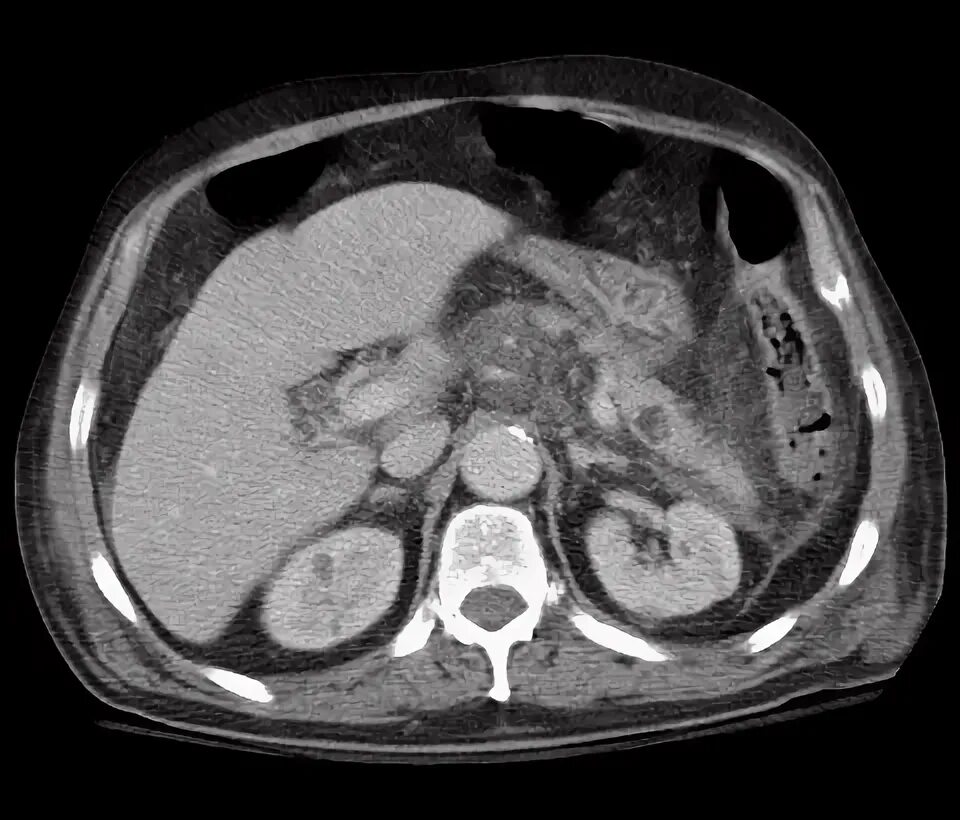

Липоматоз изменение поджелудочной железы